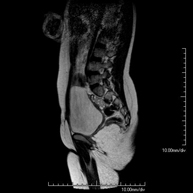

- Lumbar spine MRI

This non-invasive diagnostic procedure uses an electromagnetic field and radio waves (from a transmitter and receiver) to acquire high-definition anatomical images of the lumbar and sacral regions. It is a radiation-free procedure. Indicated for: trauma, sciatica, herniated discs, tumours, infections.